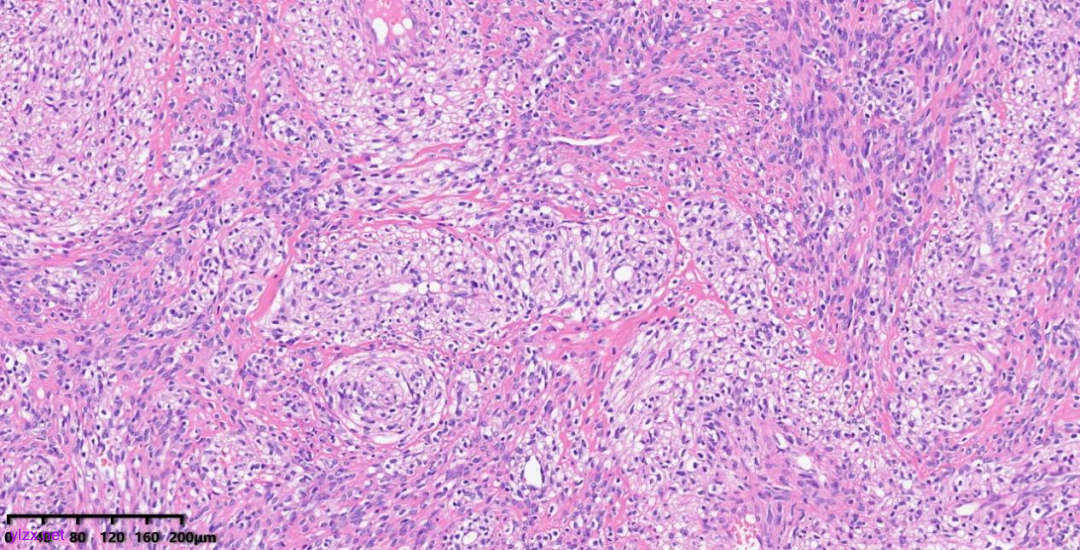

肿瘤细胞以梭形细胞、卵圆形细胞为主,部分为胞浆透亮的上皮样形态,透亮细胞界限较清,胞质淡染或胞浆丰富、嗜酸性,肿瘤内血管丰富,肿瘤细胞围绕血管周围片巢状、束状及放射状排列;肿瘤细胞核异型性不明显,核分裂像少见(<1个/50HPF),染色质开放,可见小核仁;肿瘤间质水肿、黏液变性,纤维胶原增生伴玻璃样变性。

图1~5 低倍镜下:肿瘤细胞以梭形细胞、卵圆形细胞为主,部分为胞浆透亮的上皮样形态,肿瘤细胞分布疏密不均,部分区密集丰富,部分区肿瘤细胞稀少,间质疏松水肿、黏液变性,肿瘤细胞围绕血管周围生长,局部间质纤维胶原增生伴玻璃样变性。

图6 中倍镜下:肿瘤内血管丰富,胞浆透亮的上皮样细胞围绕血管周围片巢状、束状及放射状排列。

图7~10 高倍镜下:梭形细胞、上皮样细胞组成的巢状、梁状结构,周围包绕纤细的薄壁毛细血管,肿瘤细胞呈放射状排列在血管周围,细胞界限较清,胞浆丰富、嗜酸性或透亮,细胞异型性不明显,核分裂像少见,细胞核呈圆形,染色质开放,可见小核仁;局部少量慢性炎细胞浸润。

【镜下组织形态】:

PEComas通常表现为由梭形细胞、上皮样细胞组成的巢状、梁状结构,具有丰富的颗粒状、嗜酸性或透亮胞浆,圆形细胞核及细小核仁,巢状、梁状结构周围通常包绕纤细的薄壁毛细血管,肿瘤细胞呈放射状排列在血管周围。